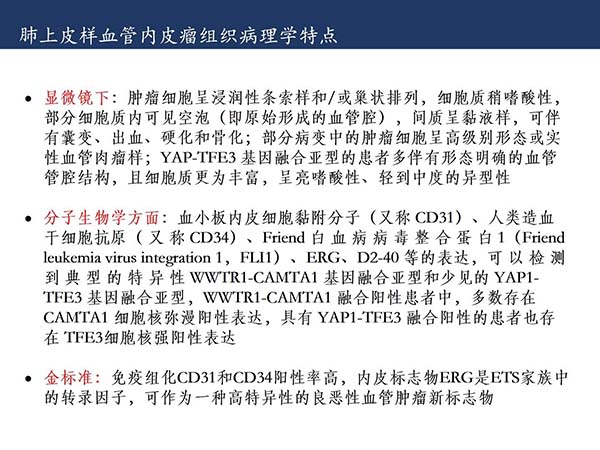

【杨柳科普】肺上皮样血管内皮瘤的影像表现